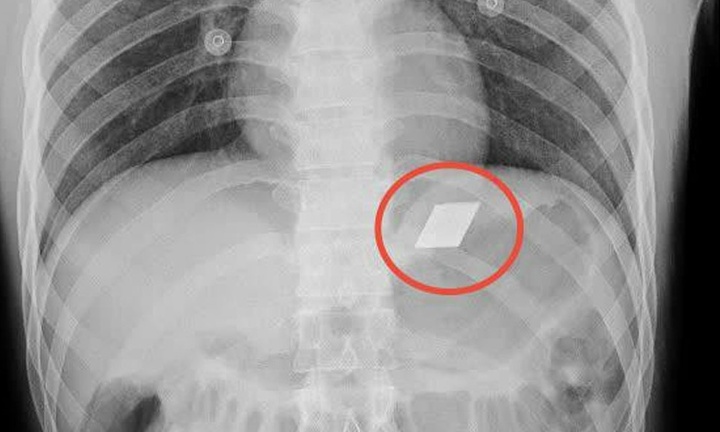

Sau khi thăm khám, các bác sĩ tại Khoa Sọ Não Cột Sống 2 đã tiến hành chụp MRI và phát hiện một khối thoát vị lớn chèn ép nặng ống sống và rễ thần kinh, thủ phạm chính gây ra cơn đau đớn vùng lưng, mông đùi phải cho người bệnh. Ngay lập tức, êkip quyết định phẫu thuật nội soi lấy thoát vị đĩa đệm – một kỹ thuật xâm lấn tối thiểu, cho phép tiếp cận chính xác khối thoát vị mà vẫn bảo tồn tối đa các mô xung quanh.